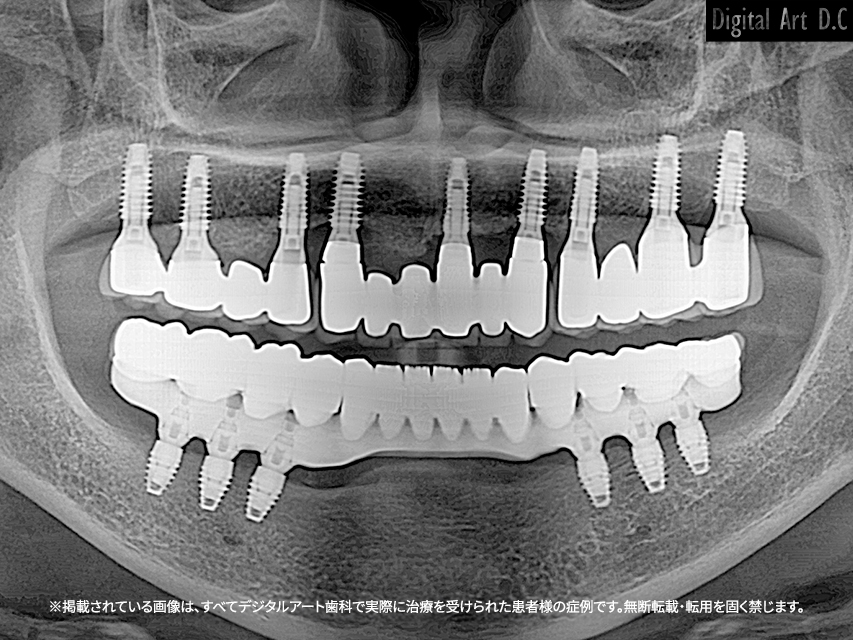

- All-on-4 / All-on-6 방식: 4~6개의 임플란트로 전체 보철물을 지지

- 초기 상담 및 3D CT 정밀 진단

- 임플란트 식립 및 임시 보철 장착

- 잇몸 회복 기간 (약 2~4개월)

- 최종 보철물 제작 및 장착